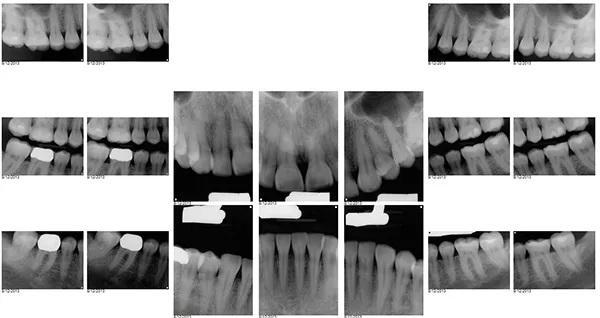

Для постоянной фиксации виниров использовался полупрозрачный цемент (RelyX Veneer Cement, 3M Oral Care) виниры были зафиксированы парами начиная с области центральных резцов, затем латеральные резцы и заканчивая клыками. Каждую реставрацию закрепляли с помощью 3-секундного светового отверждения, а излишки цемента удаляли с помощью ультразвукового скеллера. Окончательное отверждение осуществлялось путем полимерезации светом в течение дополнительных 20 секунд на каждый зуб. Результаты проведённого лечения показаны на фото с 9 по 12. Изменение улыбки пациентки с фиксированными постоянными реставрациями (фото 9). Демонстрация смыкания после лечения (фото 10). Портретная фотография анфас с широкой улыбкой (фото 11). Прицельные снимки зубов пациентки после проведенного лечения (фото 12).

Фото 12